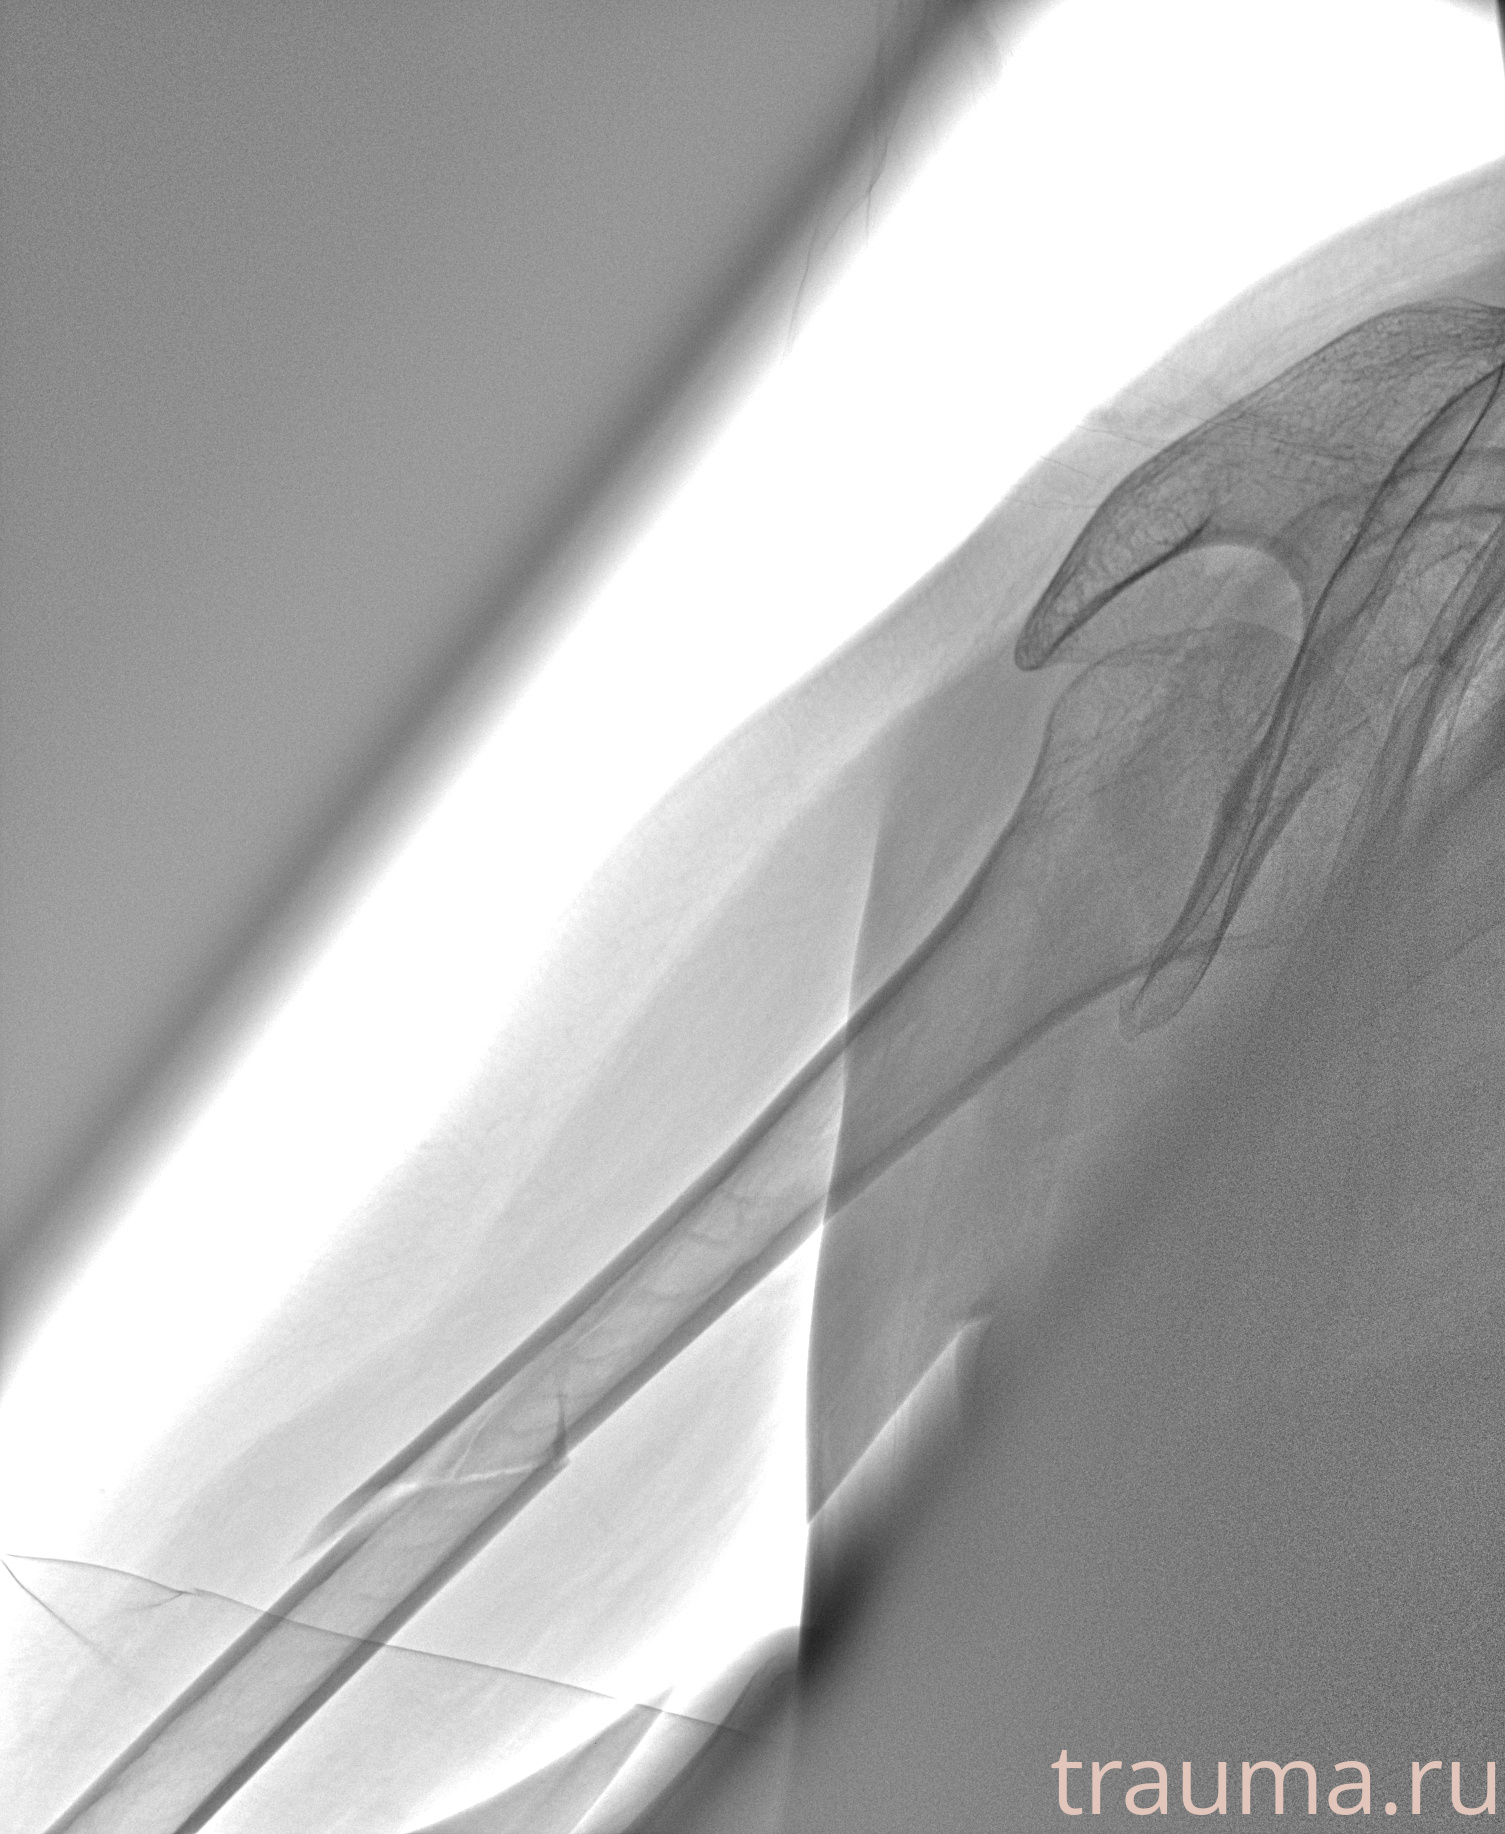

Рентген на дому: по вашему адресу приезжает врач-рентгенолог, травматолог-ортопед с мобильным рентгеновским аппаратом, проводит диагностику травмы или заболевания, делает необходимые рентгенограммы, дает рекомендации по дальнейшему лечению. Получить качественные снимки в домашних условиях возможно благодаря уникальной методике, разработанной МосРентген Центром для института  Склифосовского

при переломе шейки бедра и пневмонии от компании МосРентген Центр - партнера Института имени Склифосовского